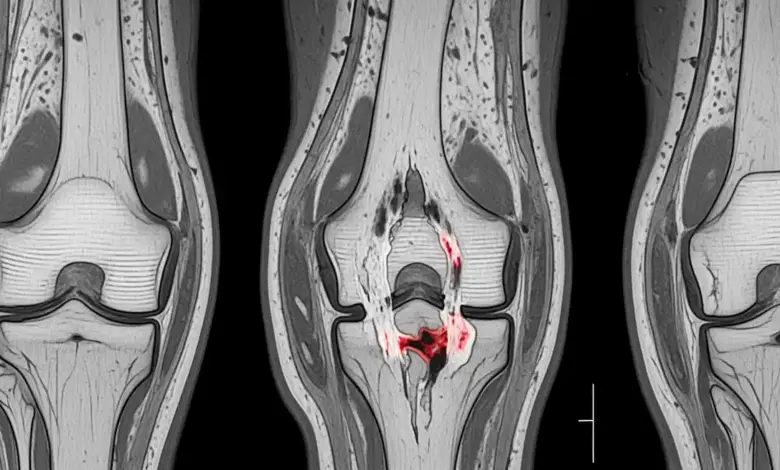

Nem toda lesão do LCA vai direto para o centro cirúrgico. A decisão depende do exame físico, da ressonância, do padrão de instabilidade e do perfil de vida do paciente.

Quando há indicação operatória, o procedimento usado é a reconstrução do LCA por artroscopia, com pequenas incisões, uso de câmera e instrumentos específicos para restaurar a estabilidade do joelho.

A reconstrução do ligamento cruzado anterior é um procedimento por vídeo, feito por artroscopia.